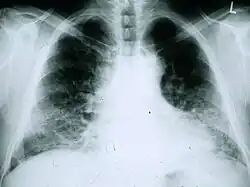

Röntgenübersichten des Thorax sind sehr nützlich bei der Verlaufsbeobachtung von IPF-Patienten. Das konventionelle Übersichtsbild führt leider zu keiner endgültigen Diagnose, kann aber ein verringertes Lungenvolumen anzeigen, typischerweise mit markanten retikulären interstitiellen Zeichnungsvermehrungen nahe der Lungenbasis.[1]

Die radiologische Untersuchung mittels HRCT ist ein grundlegendes Element der IPF-Diagnose. Ein HRCT wird mit einem konventionellen Computertomographen ohne Injektion eines Kontrastmittels durchgeführt. Die Schnittbilder zur Auswertung sind sehr dünn (1–2 mm).

Ein typisches Thorax-HRCT bei IPF weist fibrotische Veränderungen beider Lungenflügel auf, vor allem im Bereich der Basis und der Peripherie. Gemäß der gemeinsamen ATS/ERS/JRS/ALAT-Richtlinien von 2011 ist das HRCT ein maßgeblicher Bestandteil im diagnostischen Prozess der IPF, da es eine UIP bei Vorliegen folgender Merkmale identifizieren kann:[1]

- Retikuläre Verschattungen, die oft mit Traktionsbronchiektasie einhergehen

- Honigwabenmuster, gekennzeichnet durch Ansammlungen zystischer Lufträume, die meistens einen vergleichbaren Durchmesser haben (3–10 mm), gelegentlich aber auch größer sind. Sie liegen für gewöhnlich subpleural und sind durch klar abgegrenzte Wände und das Auftreten in mindestens zwei Reihen gekennzeichnet. Eine Reihe von Zysten reicht nicht aus, um als Honigwabenmuster bezeichnet zu werden.

- Milchglasverschattungen sind häufig, doch weniger ausgedehnt als die Netzstruktur.

- Die Verteilung ist typischerweise basal und peripher, jedoch häufig auch fleckförmig.